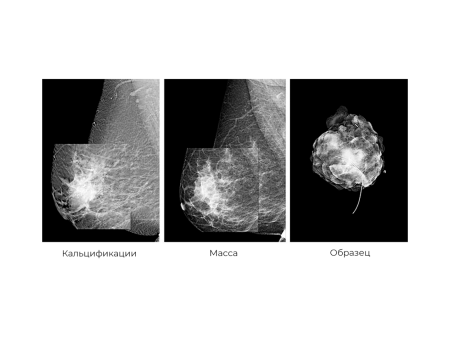

Система поразительно точно выявляет самые первые признаки рака, начиная с 1 стадии: мельчайшие скопления солей кальция размером от 57 мкм, фиброзные тяжи и прочее. Это становится возможным благодаря инновационному детектору прямого преобразования на основе аморфного селена (a-Se) с квантовой эффективностью более 70%! Врач не пропустит даже малоконтрастные опухоли, начальный воспалительный процесс и кисты благодаря высокой четкости и информативности изображений.

После этого лаборант занимает рабочее место за рентгенозащитным стеклом и запускает сканирование. Во время процедуры женщина стоит неподвижно и не дышит несколько минут. На грудь подается небольшое количество рентгеновского излучения. Оно проходит сквозь ткани и фиксируется цифровым детектором. Через несколько секунд информация появляется на мониторе в виде черно-белого 2D изображения.